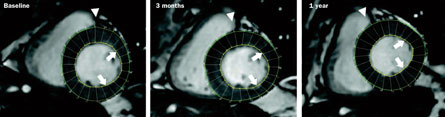

“The totality of evidence from the clinical trials is positive,” says Hare, who is conducting some of the trials and is on the board of Stem Cell Therapeutics, a Canadian-based company. “The heart is pumping more blood per beat.” In March in the journal Circulation Research, his team described a study of eight patients who received injections of bone marrow cells near an area of the heart scarred due to heart attack. After three months, the patients’ heart contractions were stronger. Even more important, their hearts later appeared to undergo some degree of “reverse remodeling,” or an attempt to return to normal anatomy, though the precise mechanism isn’t known.